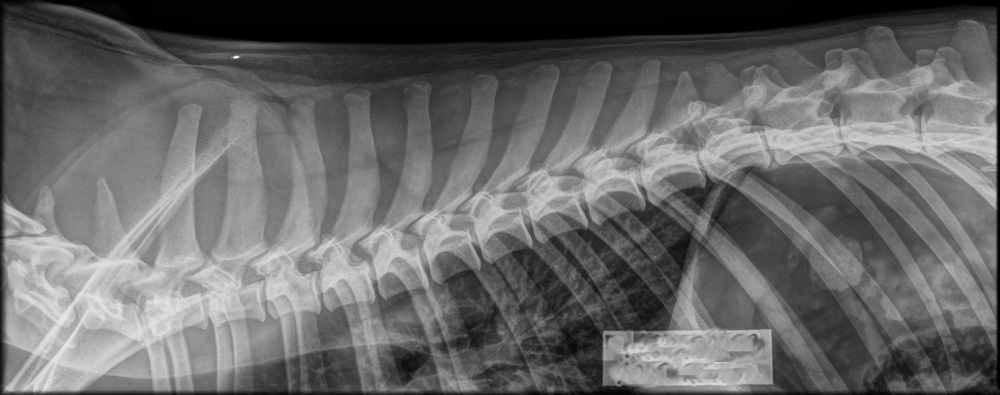

Broholminkoirilla seurattavia ja rodussa esiintyviä tuki- ja liikuntaelimistön sairauksia ovat muun muassa selän spondyloosia, joka on selkärangan rappeuttava sairaus ja voi ilmetä erityisesti iän myötä. Lonkkanivelen dysplasia (HD) ja kyynärniveldysplasia (ED), jotka voivat vaikuttaa koiran liikkuvuuteen ja elämänlaatuun eri asteisesti.

Spondyloosi on selkärangan rappeuttava sairaus, jossa nikamien väliin muodostuu luusiltoja. Muutokset kehittyvät yleensä hitaasti ja voivat olla pitkään oireettomia. Oireisena spondyloosi voi aiheuttaa jäykkyyttä, liikkumishaluttomuutta tai kipua. Sairauden ilmeneminen lisääntyy iän myötä, ja sen vaikutuksia voidaan usein lieventää oikealla liikunnalla, lihaskunnon ylläpidolla ja painonhallinnalla.